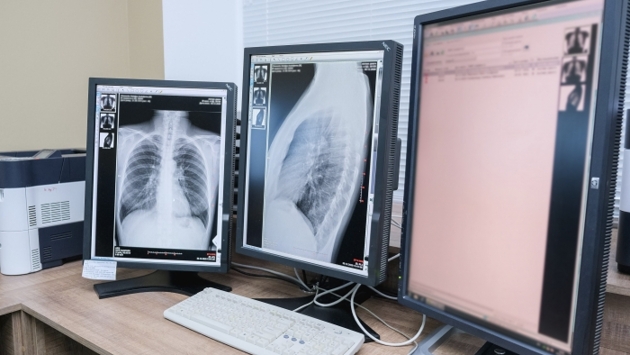

8 ноября в мире отмечают День рентгенолога, в этот день 126 лет назад немецкий физик Вильгельм Конрад Рентген открыл рентгеновское излучение. Врач-рентгенолог Фарида Курбанова ответила на популярные вопросы об этом самом доступном методе диагностики.

Чаще всего у пациентов возникают опасения относительно того, что после частых рентген-исследований могут развиваться онкологические заболевания. По словам медика, определенные риски действительно есть, но крайне невысокие.

− Вероятность возникновения рака есть при любом радиационном воздействии: как и в обычной жизни при поездке в метро, путешествии на самолете и прохождении через сканер в аэропорту во время предполетного досмотра, − рассказывает Фарида Курбанова. – Поэтому, если исследование необходимо ребенку или взрослому по жизненным или абсолютным показаниям, риск его проведения оправдан, потому что польза явно превышает потенциальный вред.

Для сравнения: солнечное излучение обладает более мощным спектром как гамма-излучения, так и других его видов. Поэтому флюорография приносит намного меньше вреда, подчеркивает рентгенолог.